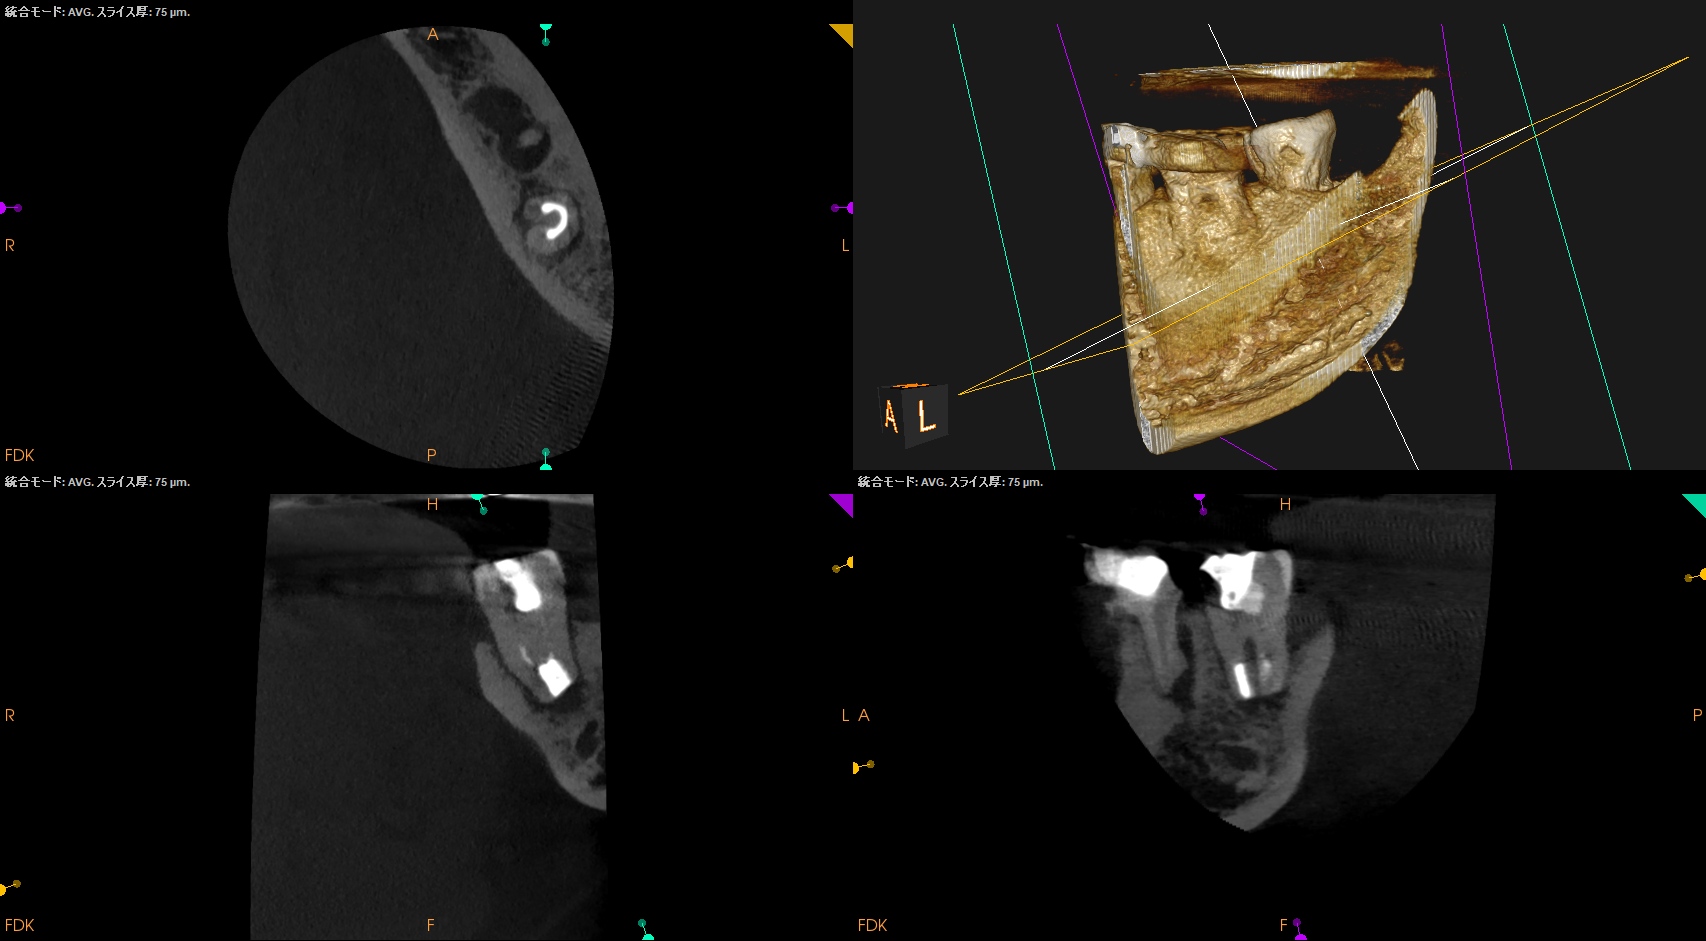

CBCT(2025.12.10)

ML

MB

D

遠心方向から見ると、

絶望的な状態であることがわかる。

抜歯し、口腔外で虫歯を除去し、Apicoectomyして抜歯窩へ戻すIntentional Replantationを行う必要があるだろう。